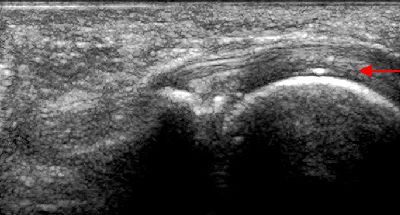

Calcificazione capsula articolare Calcificazione capsula articolare